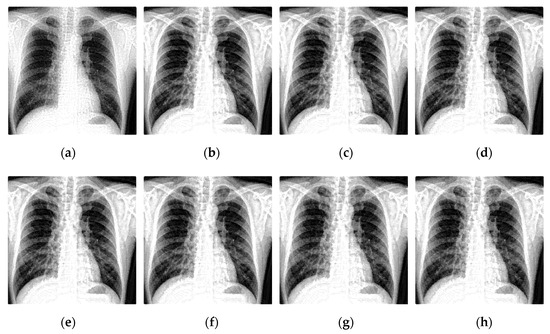

Select two representative medical images for analysis: Image 1 with the size of 440 × 440 and image 2 with the size of 1024 × 1024 . The enhanced X-ray images obtained under different decomposition levels are shown in Figure 3 and Figure 4 where (a) is the original image, and (b–f) corresponds to the decomposition levels j equal to 1–5. When the number of scale decomposition levels is j , NSST decomposition requires 2 j times of image and filter convolution; the running time of the algorithm gradually increases. Observing the image, the image contrast has been significantly improved after histogram equalization. When the decomposition scale j 3 , with the increase of the NSST decomposition scale, the boundary and texture features of the image are gradually obvious, and the detailed information is enhanced. When 5 j > 3 , the enhancement effect is further improved; the change is not significant.

Figure 3. The enhanced effects of different decomposition levels on the X-ray image 1. (a) is the original image, and (bf) corresponds to the decomposition levels j equal to 1–5.